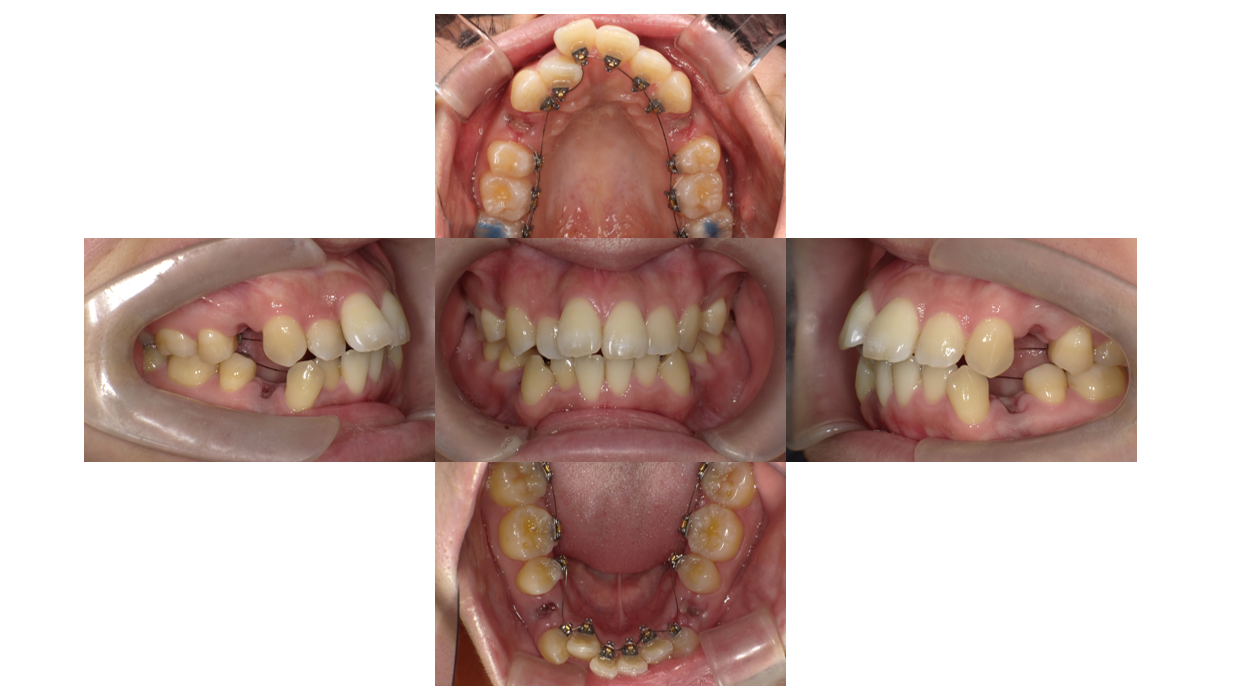

Before

叢生改善・出っ歯改善・裏側(リンガル)矯正

装着を装着しました。

奥歯にバイトアップを装着することで、装置が外れにくくしています。